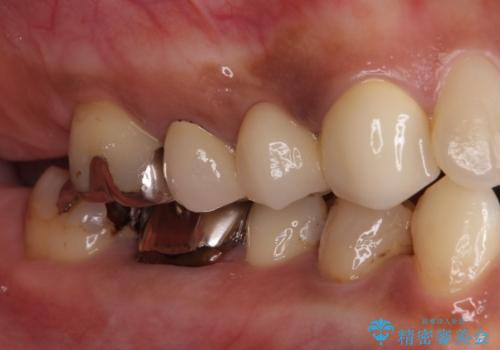

他にも、奥歯の銀歯の下にもむし歯が多くあり、痛みが生じていたため、根管治療などを行った上で、オールセラミッククラウンにて補綴治療することとしました。